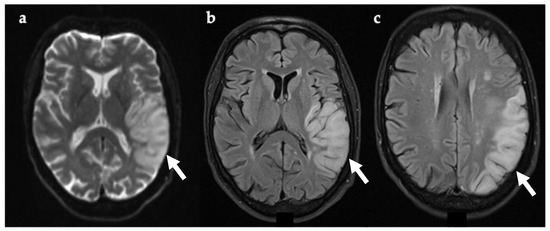

During the most recent admission, septic and vasculitis screens, including ESR and C-reactive protein, were normal. Brain MRI (Figure 4) showed multiple areas of increased T2w signal in the cortex and white matter of the posterior cerebral hemispheres, with overlap between old and recent lesions. Magnetic resonance angiography (MRA) was normal (Figure 4). CSF was acellular with normal protein and glucose levels, but raised lactate (4 mmol/L, reference range 1.1–2.4 mmol/L). CSF viral PCR was negative. Status epilepticus was treated with intravenous diazepam and clobazam, levetiracetam, and lamotrigine.

Figure 4. (a) Axial brain MRI image taken four days after symptom onset, showing multiple areas of white matter and cortical increased T2w signal within the posterior cerebral hemispheres (white asterix). DWI is not available. (b) Normal MRA with no evidence of narrowing of blood vessels, as usually present in CNS vasculitis. DWI, diffusion-weighted imaging; MRA, magnetic resonance angiography; T2w, T2-weighted imaging.